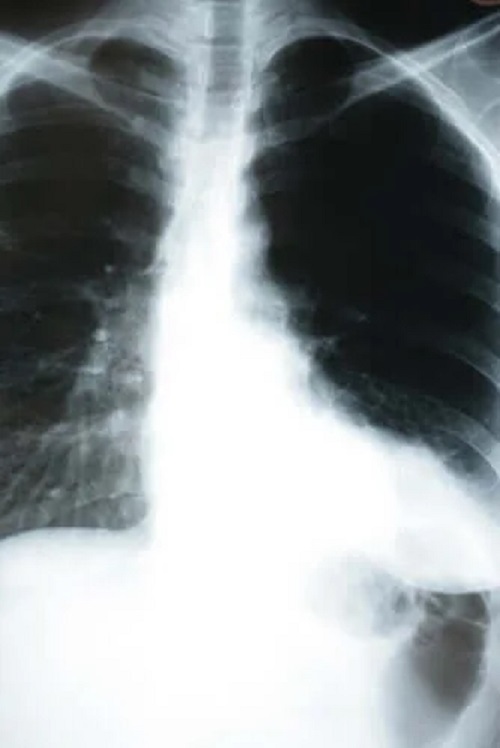

La pacienții cu pneumonie silențioasă, este valabil tocmai opusul. În mai multe spitale din New York și Brazilia, numeroși pacienți au fost diagnosticați cu pneumonie silențioasă, deși aparent se simțeau bine. Cu toate acestea, medicii au descoperit pneumonia silențioasă prin măsurarea nivelului de oxigen din sânge sau prin radiografia toracică.

Așadar, dacă bănuiești că ai putea avea coronavirus, roagă medicul să îți măsoare nivelul saturației de oxigen din sânge și chiar să-ți facă o radiografie toracică. Acest lucru este deosebit de important dacă ai intrat în contact cu cineva infectat sau dacă te afli într-una dintre grupele de risc.